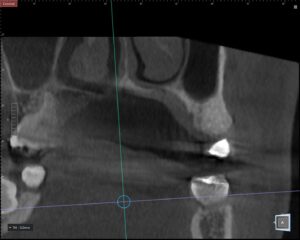

そのため当院では、CTによる精密診断を行い、無理のない治療計画を立てています。

✔ CTを用いた精密診断

デジタル診断とワンガイドシステムによる精密治療

特にオステムインプラントでは、**デジタルシミュレーションとガイド手術(ワンガイドシステム)**を活用しています。事前にCTデータをもとに埋入位置をシミュレーションし、専用のガイドを使用して手術を行うことで、

・埋入位置の精度向上

・手術時間の短縮

・身体的負担の軽減

が期待できます。手術時間が短縮されることで、結果的に患者様の不安や緊張の軽減にもつながります。

インプラント治療では、無理のない位置・角度で埋入することが重要です。事前のデジタル設計により、

余分な切開や骨への負担を抑えることが可能になります。これが、「思っていたより楽だった」というお声につながっている理由の一つです。

診断結果|歯根破折の可能性

CT撮影を行ったところ、歯根に亀裂が疑われる所見がありました。この状態では、再度の根管治療での長期保存は難しく、抜歯が適応となるケースでした。患者様は

事前にCTデータをもとにデジタルシミュレーションを行い、埋入位置を設計。

今回はオステムインプラントのワンガイドシステムを使用しました。ガイドを用いることで、

事前に計画した位置へ正確に埋入することが可能になります。